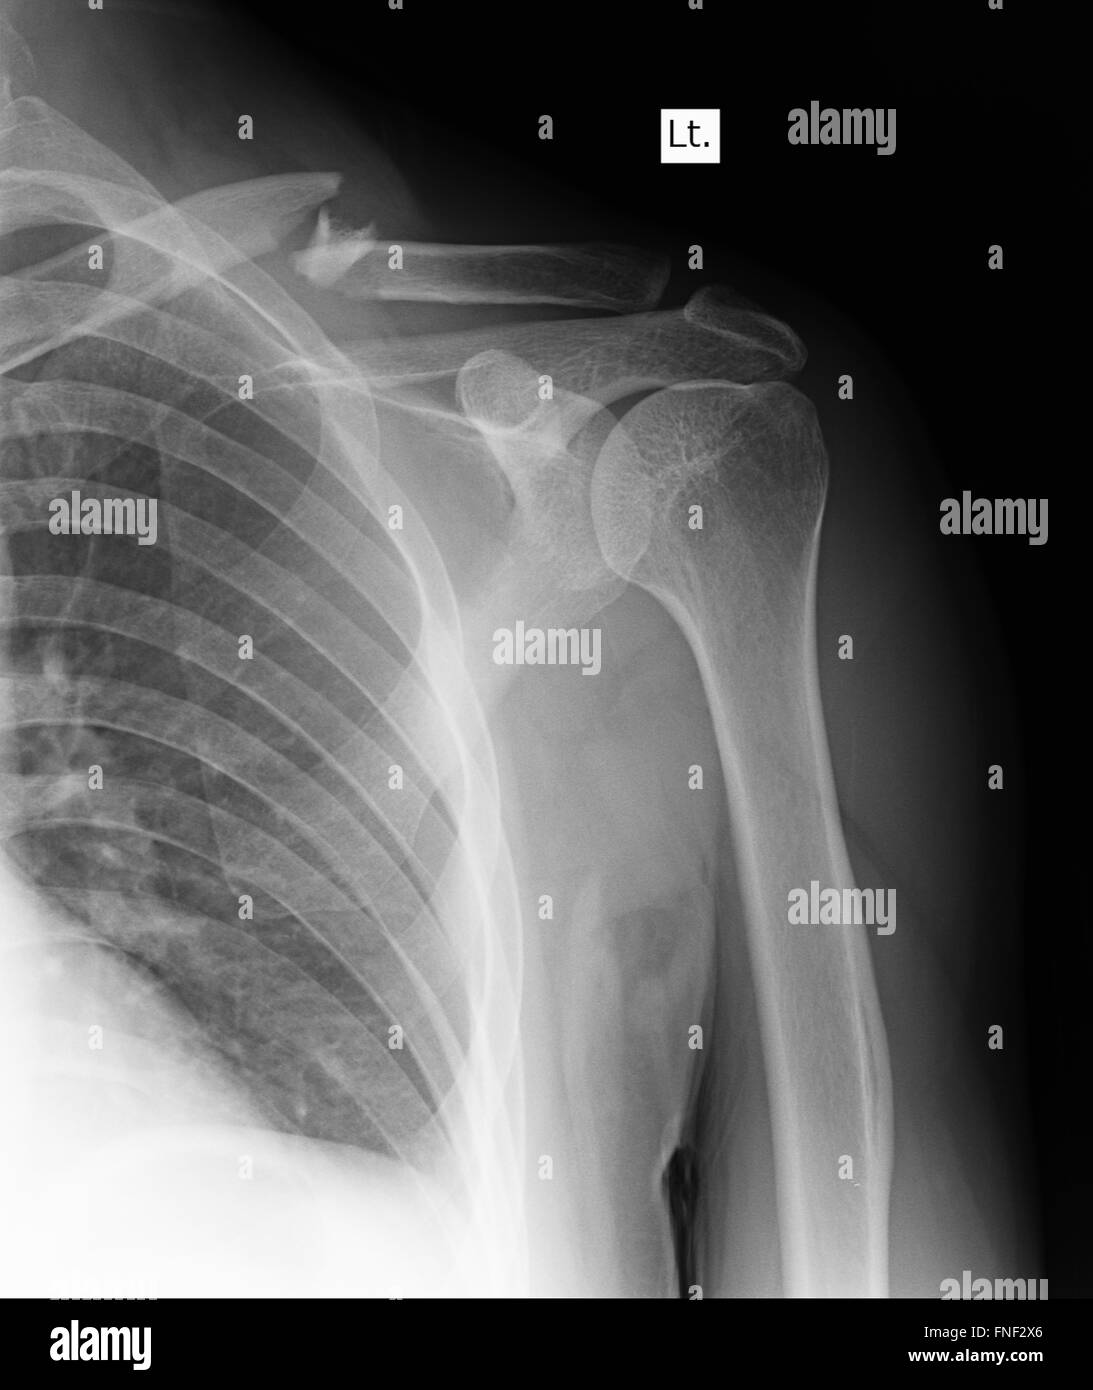

Xray Shoulder Joint Shoulder Front View for Diagnosis Fracture of X Ray Of Shoulder Soft tissue areas, cortical margins, trabecular. Shoulder radiographs are often the only imaging exam necessary for the evaluation of acute shoulder trauma, calcific tendonitis,. The shoulder series is fundamentally composed of two orthogonal views of the glenohumeral joint including the entire. A recommended systematic checklist for reviewing musculoskeletal exams is: The shoulder ap view is a standard projection that makes. X Ray Of Shoulder.

X Ray Of Shoulder . The shoulder ap view is a standard projection that makes up the two view shoulder series. Shoulder radiographs are often the only imaging exam necessary for the evaluation of acute shoulder trauma, calcific tendonitis,. A recommended systematic checklist for reviewing musculoskeletal exams is: The shoulder series is fundamentally composed of two orthogonal views of the glenohumeral joint including the entire. Soft tissue areas, cortical margins, trabecular.